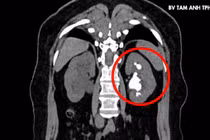

Tại khoa Nhi, Bệnh viện Đa khoa Tâm Anh Hà Nội, kết quả phân tích và nuôi cấy nước tiểu xác định bé nhiễm trùng đường tiểu do vi khuẩn Enterococcus faecalis và được điều trị kháng sinh theo phác đồ, theo dõi sát diễn tiến bệnh nhằm phát hiện sớm biến chứng.

Ngày thứ hai, trẻ xuất hiện triệu chứng thóp phồng căng, lơ mơ. Bác sĩ chỉ định siêu âm thóp để tầm soát tổn thương thần kinh nhưng chưa ghi nhận bất thường.

Tuy nhiên, các xét nghiệm cho thấy tình trạng viêm nặng khi chỉ số CRP tăng lên 22,7 mg/dL, cao gấp hơn 40 lần ngưỡng bình thường. Đáng chú ý, nồng độ Procalcitonin (PCT) đạt 4 ng/mL, gợi ý nhiễm trùng nặng, nguy cơ cao tiến triển nhiễm khuẩn toàn thân và nhiễm trùng huyết.

Trước nguy cơ biến chứng thần kinh, bác sĩ chỉ định cấy máu kết hợp chọc dò dịch não tủy và các xét nghiệm chuyên sâu, kết quả xác định bệnh nhi bị viêm màng não. Đây là tình trạng các màng bao quanh não và tủy sống bị nhiễm trùng khi vi khuẩn, virus, nấm theo đường máu xâm nhập hệ thần kinh trung ương.

Bác sĩ chẩn đoán bé Ánh đồng thời mắc viêm mũi họng, nhiễm khuẩn tiết niệu biến chứng nhiễm khuẩn huyết và viêm màng não. Bé được điều trị tích cực bằng kháng sinh theo phác đồ phù hợp nhằm kiểm soát ổ nhiễm trùng, ngăn tổn thương lan rộng lên não và hệ thần kinh.